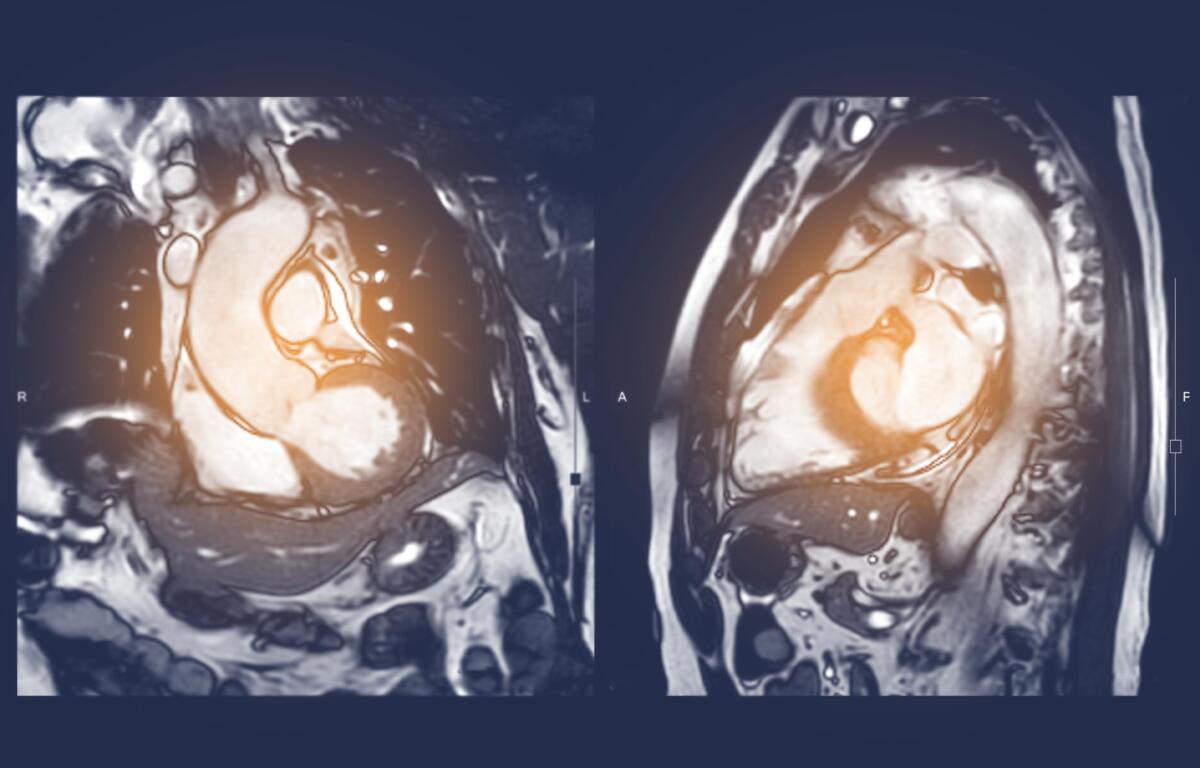

The researchers, led by the University of Virginia Department of Biomedical Engineering’s Frederick H. Epstein, developed an innovative way to use magnetic resonance imaging, or MRI, to assess the composition of adipose tissue – fat – surrounding the heart. That test could help identify patients at greatest risk for potentially deadly cardiac problems such as coronary artery disease, atrial fibrillation (irregular heartbeat) and heart failure, and predict how patients may respond to treatment.

The MRIs would let doctors see inside the body without surgery. By analyzing the amounts of saturated fatty acids, monosaturated fatty acids and polyunsaturated fatty acids, doctors could be able to identify patients who could face heart problems before symptoms appear. Identifying and correcting this problem has the potential to slow down the progression of heart disease, the No. 1 cause of death in the United States and around the world.